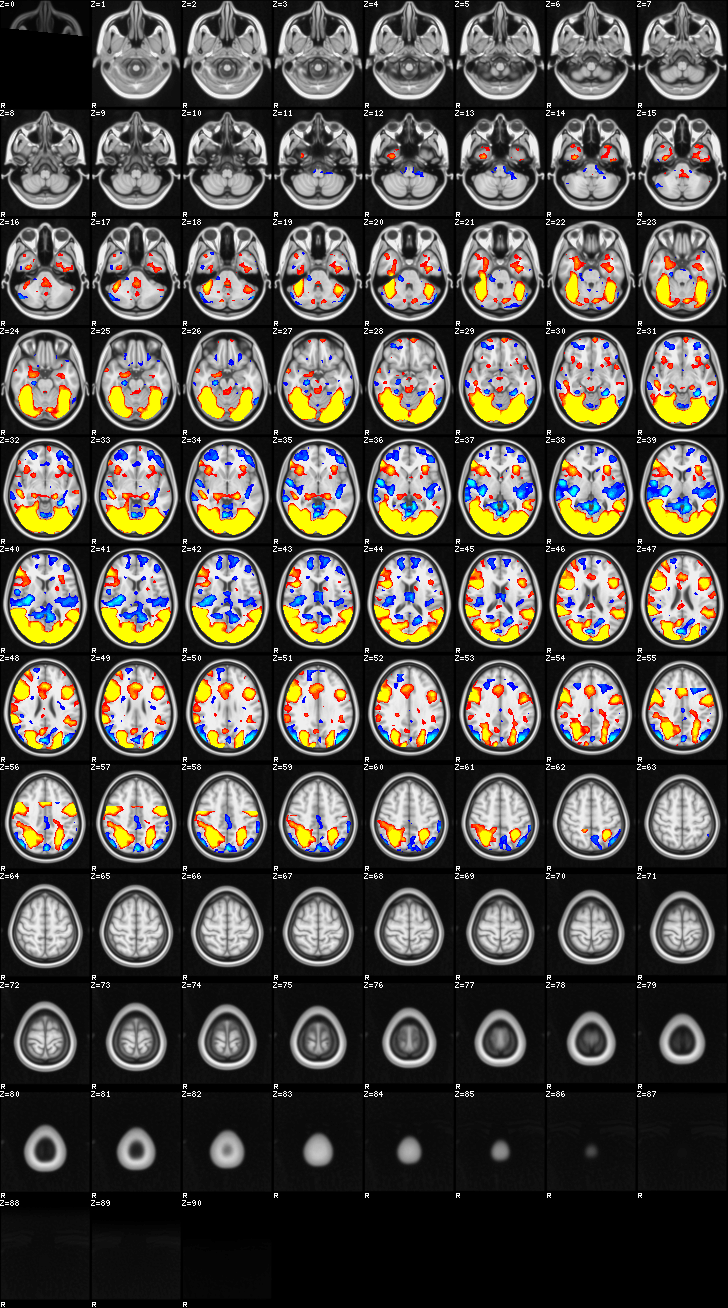

Fixed Effect¶

ATM it is 8 subjects, 8 mm FWHM spatial smoothing, preliminary results only

Images thresholded abs value > 2.3 and colormap goes from 2.3 to 5 (red->yellow) or -2.3 to -5 (blue->lightblue)

- MOTOR

- Although based on the subject responses, since they occurred only during oddball, it reflects both oddball and motor reaction

02-MOTOR¶